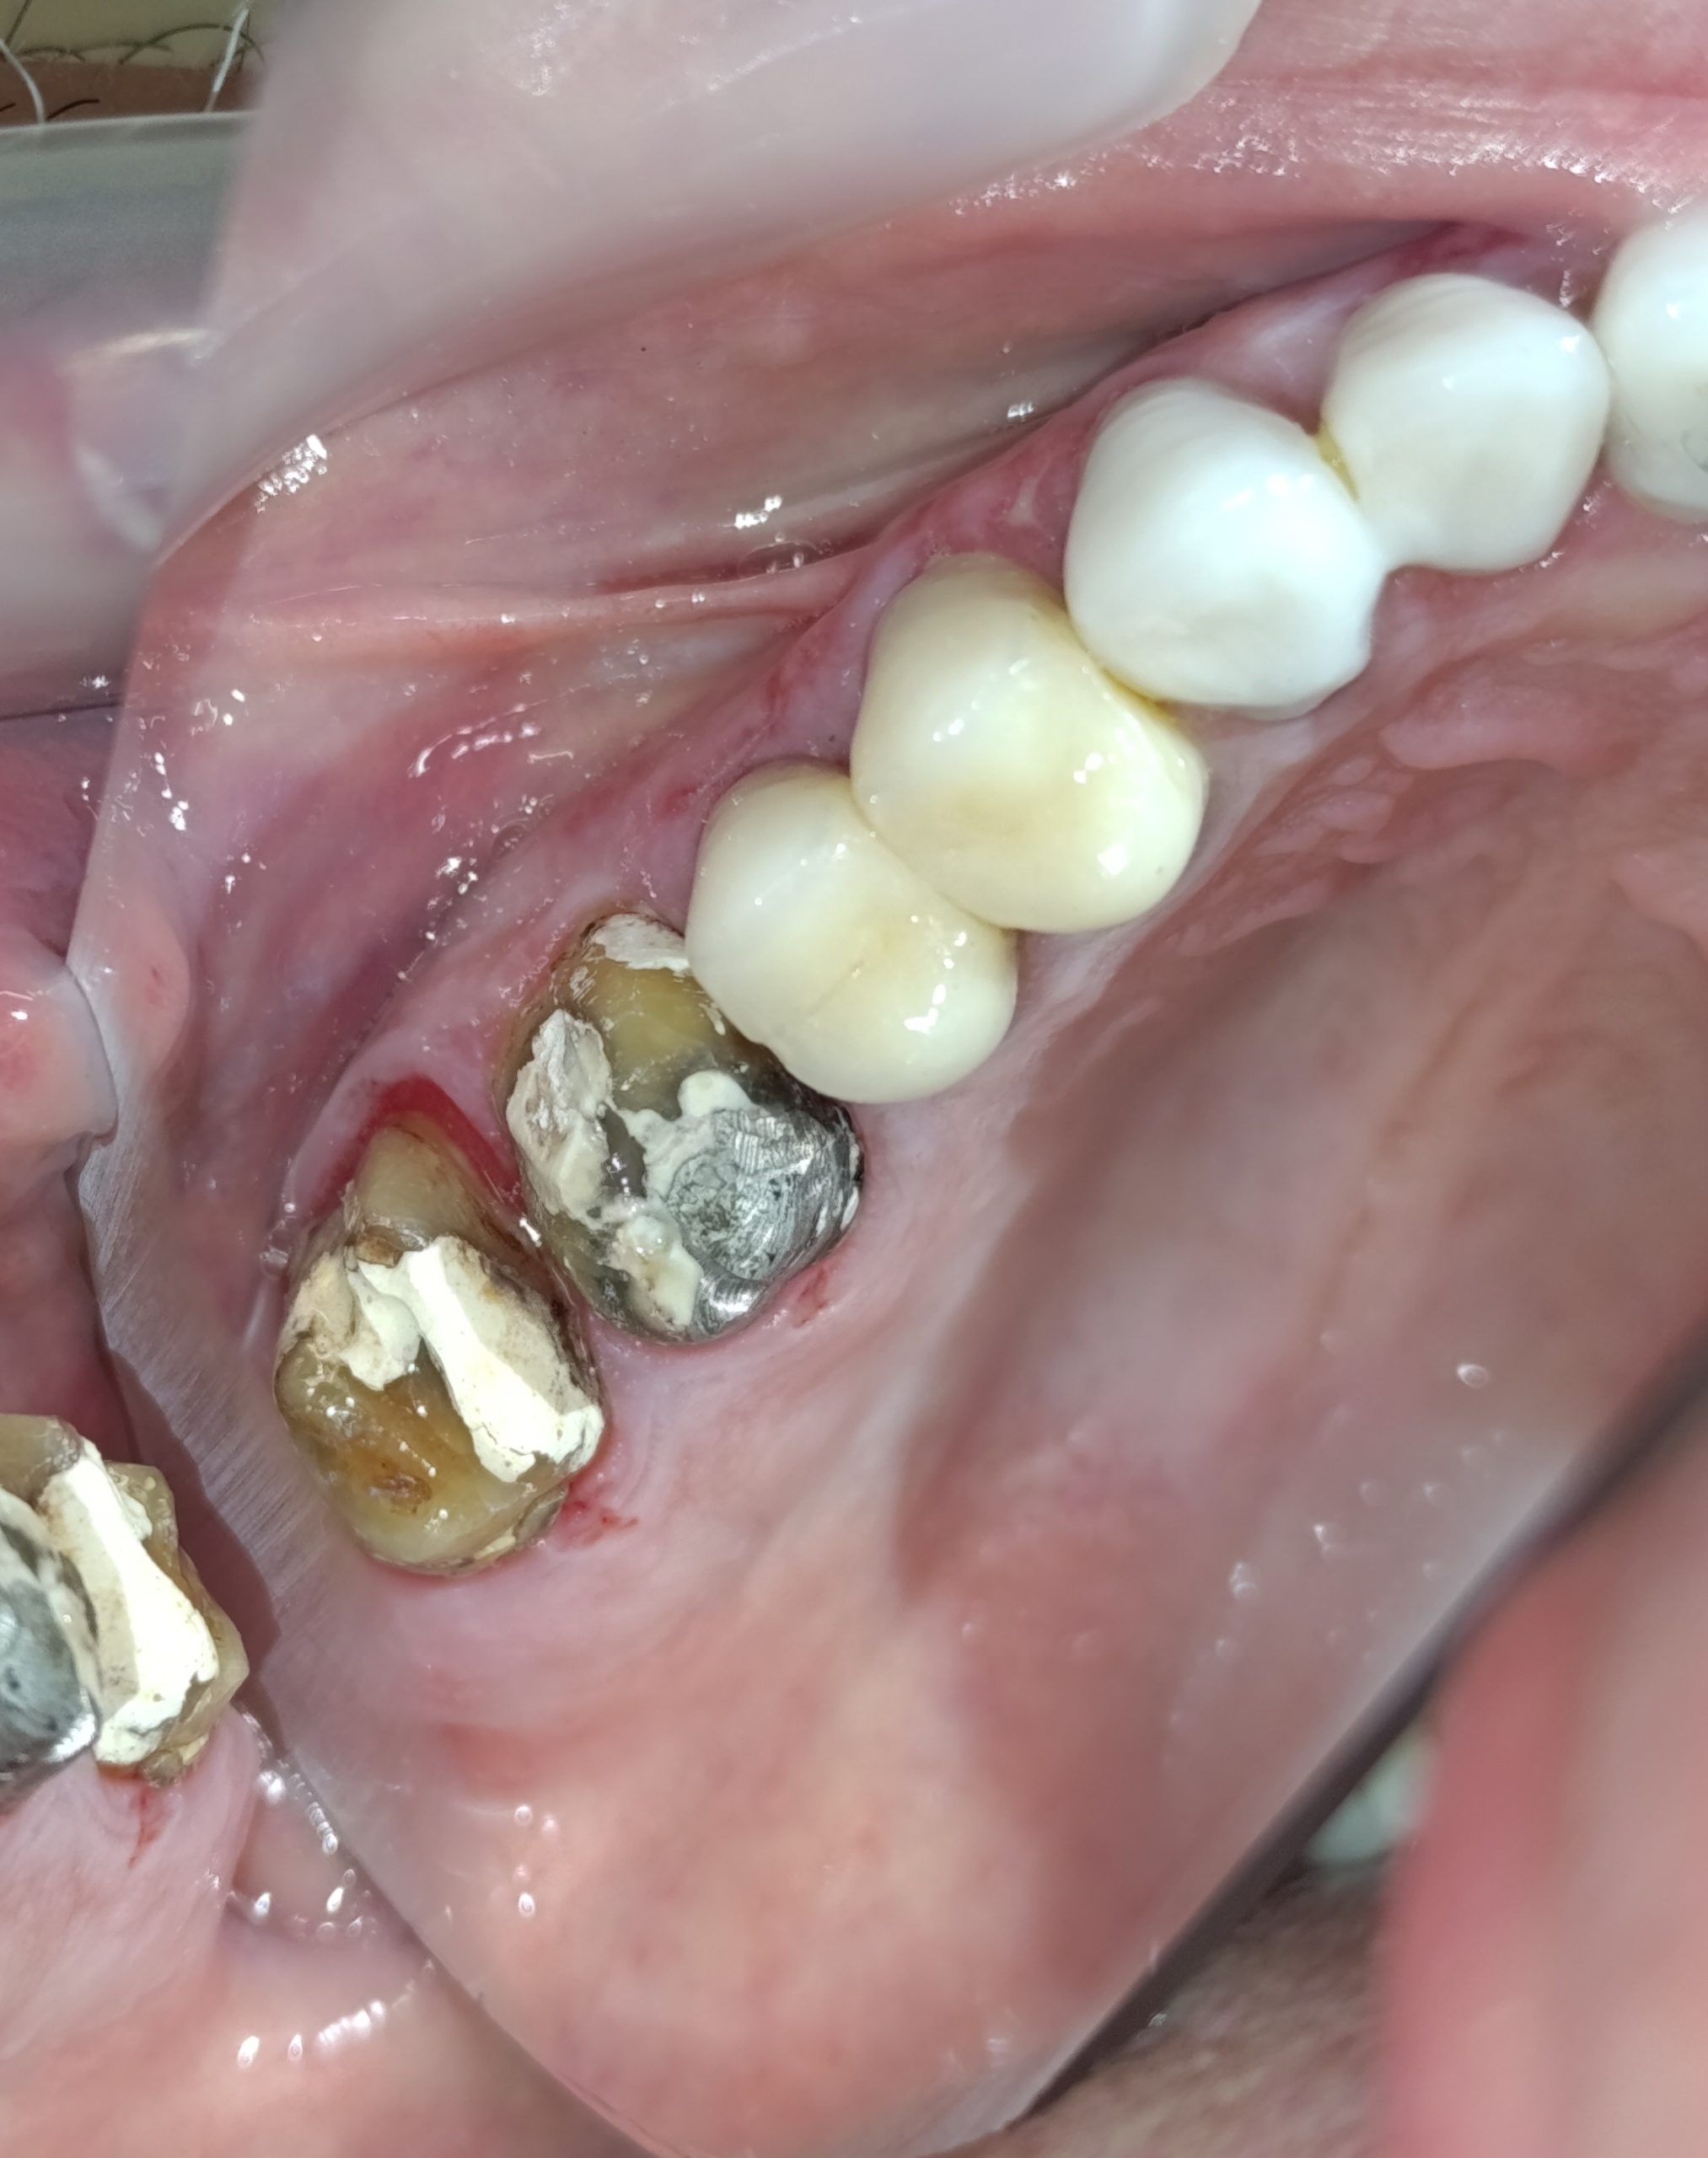

Ο ασθενής είχε δύο παλιές μεταλλοκεραμικές θήκες, οι οποίες με την πάροδο του χρόνου τερηδονίστηκαν, φθάρθηκαν (είχε φθαρεί η κεραμική κάλυψη των θηκών) και έπρεπε να αντικατασταθούν με νέες (απουσιάζει η φωτογραφία της αρχικής εικόνας). Εφόσον αφαιρέθηκαν οι παλιές θήκες πραγματοποιήθηκαν όλες οι απαραίτητες οδοντιατρικές εργασίες (απονεύρωσεις δοντιών, ανασύστασεις / σφραγίσματα δοντιών) όπου ήταν απαραίτητο, προκειμένου να κατασκευαστούν νέες ολοκεραμικές θήκες ζιρκονίου.

Στο μεσοδιάστημα που μεσολάβησε ώστε ο οδοντοτεχνίτης να κατασκευάσει τις νέες θήκες δοντιών, τα τροχισμένα δόντια ήταν προστατευμένα με προσωρινές στεφάνες.

Η νέα γέφυρα είχε ένα πολύ καλό αισθητικό και λειτουργικό αποτέλεσμα.

Αρχική εικόνα των δοντιών μετά την αφαίρεση της παλιάς γέφυρας

Τα δόντια μετά τις απαραίτητες απονευρώσεις και τις ανασυστάσεις